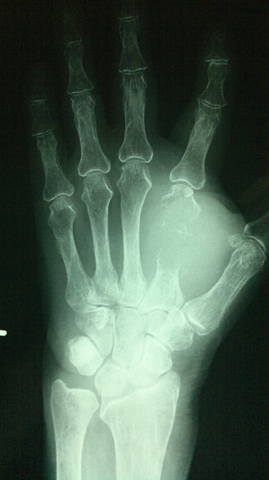

Метастаз во 2-ю пястную кость левой кисти

<br /><br />Женщина, 60 лет. Плазмоцитома.<br /><br />Опухолевый узел в области кисти болел и увеличивался в размерах с течением времени не смотря на проводимое лечение.<br /><br />

<br /><br />Выполнена ампутация 2 луча левой кисти в пределах здоровых тканей.